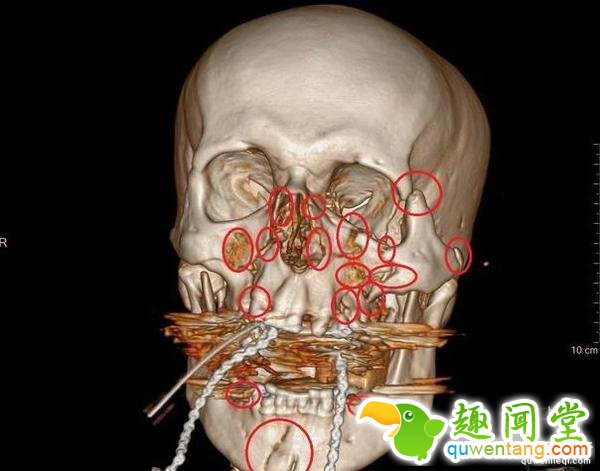

下巴粉碎,左眼眶被撞得往左移了一厘米,鼻梁就更不用说了,当时的x光片记录下这一切,Andy Robinson能活下来已经是一个奇迹。

在医治过程中,医生用了13块金属板和52个螺钉固定头骨,然后是艰难和复杂的脸部修复手术,康复后,Andy Robinson的脸上如果不仔细看,是看不出手术痕迹的,如今,为了以防万一,他不准自己的儿子骑自行车和摩托车。